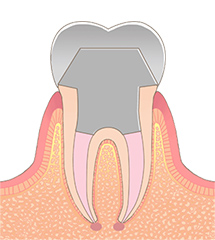

STEP06形成・印象

コアの型取りを行った場合、土台となるコアを取り付けてから、被せ物を作るために、歯の形を整え、再度型取りを行います。

可能な限り精密な型取りを行うことで、よりお口の中に合った被せ物を作ることができます。被せ物の作製は1週間ほどかかります。 -